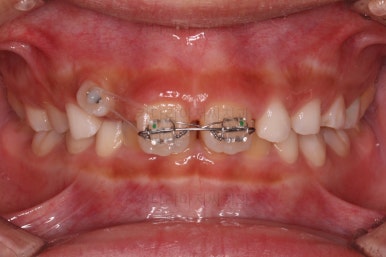

간단하게 장치를 부착하고 경로가 심하게 벗어나 있는 치아를 원위치로 당겨줍니다.

성장교정에 앞서 이러한 치아배열 작업을 약 5개월 정도 해주었어요.

문제가 되었던 치아를 제위치 시켜준 뒤에 본격적인 성장교정을 시작했어요.